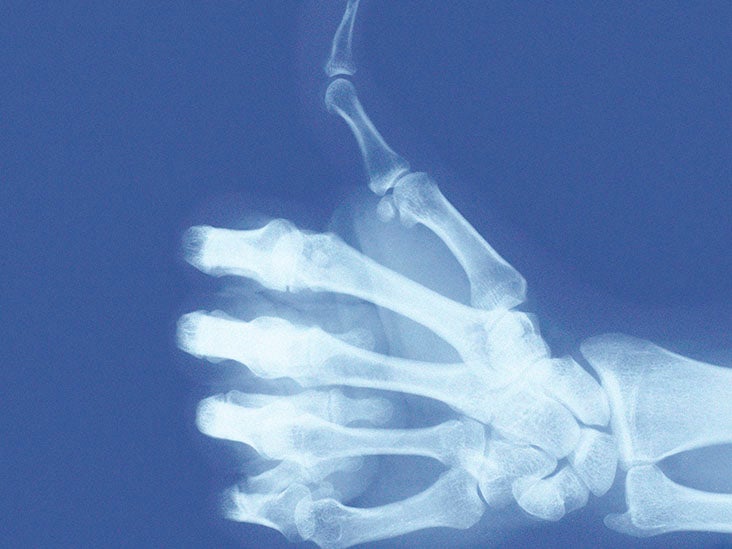

From www.medicalnewstoday.com

Thumb arthritis Symptoms, causes, and treatment Can Arthritis In Thumb Be Fixed Learn about symptoms and treatment options like exercise, medication, splints, and surgery. Using your thumb a lot can lead to osteoarthritis pain. Avoiding activities that cause pain, if possible. A pharmacist or your family doctor can advise. What can be done for arthritis in the thumb? The exact causes are not. Thumb arthritis presents with a range of symptoms that. Can Arthritis In Thumb Be Fixed.